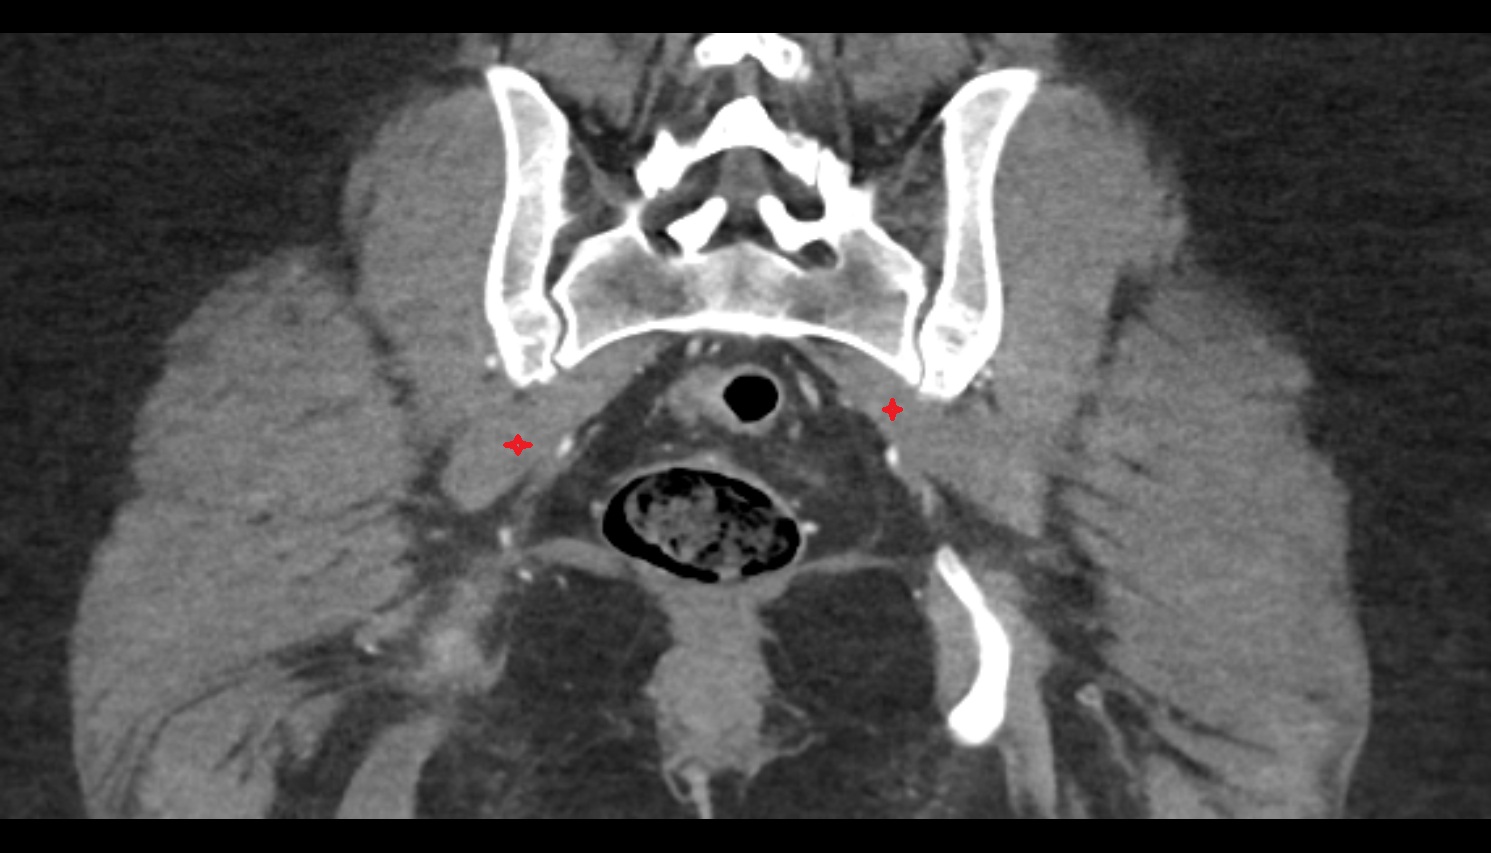

- Piriformis muscle

- Obturator internus muscle